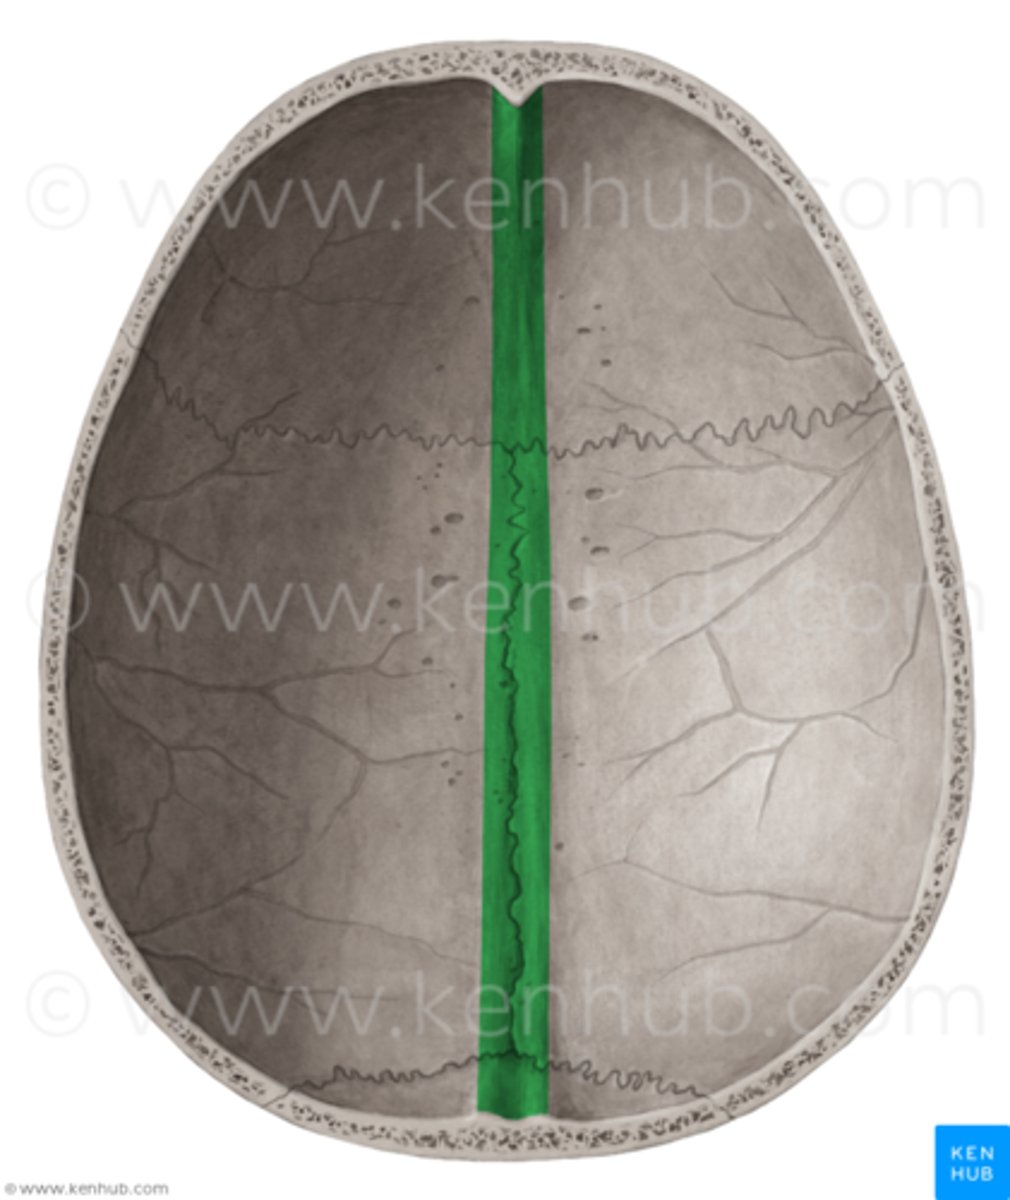

groove for superior sagittal sinus of parietal bone

right down the two hemispheres this groove exists

sagittal suture

between the two parietal bones